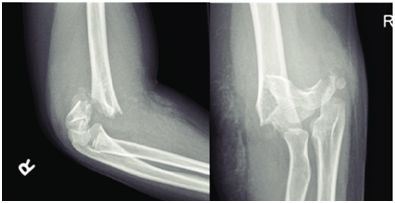

4.屈曲型

多系肘关节屈曲位,肘后着地,尺骨鹰嘴直接撞击肱骨髁部,使髁上部骨折。骨折远侧段向前移位,近侧段骨端向后移位。骨折线自前上方斜向后下方。

2.X线检查:可见骨折线。